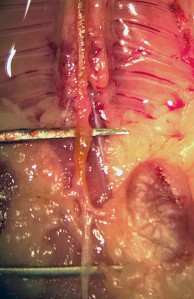

- Aortic Harvest with ex vivo measurement of aortic diameter

A formations, 28 Days Ang II, 90 Days 60% High Fat Diet